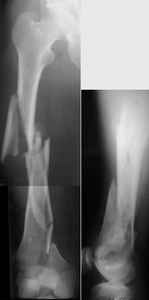

I presented a series of ~25 such cases at EuroTrauma'2004. Many cases were discussed here. I attach am example. Look also recent cases at http://www.hwbf.org/hwb/conf/alex58/scfx.htm,

I do realize that you are master surgeon, and congratulations on another excellent, spectacular case (result), but,

THX, initial images are

1,

2.

At that moment we had in stock only the 10 mm solid nails so of course there was no idea about early weight bearing. But it was quite enough for early knee ROM excersises (see attached). Two locking screws through the distal block provided that.